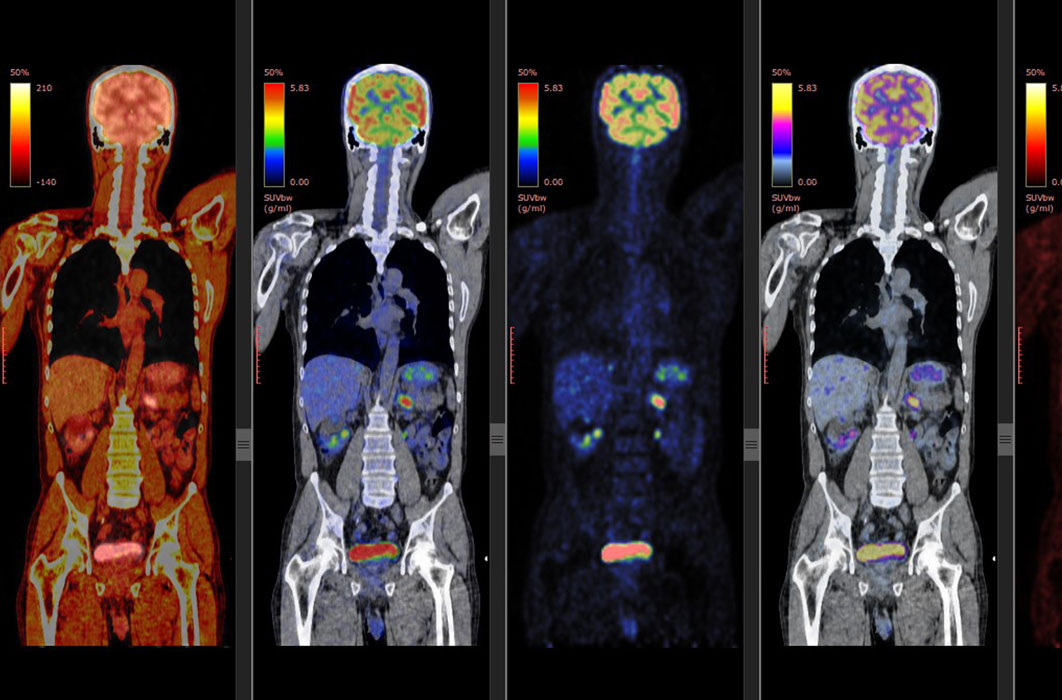

Cardiac Pet/ct

Enhance your business with our stunning commercial Cardiac Pet/ct collection of numerous professional images. optimized for commercial use with truck, vehicle, and automobile. ideal for corporate communications and branding. Discover high-resolution Cardiac Pet/ct images optimized for various applications. Suitable for various applications including web design, social media, personal projects, and digital content creation All Cardiac Pet/ct images are available in high resolution with professional-grade quality, optimized for both digital and print applications, and include comprehensive metadata for easy organization and usage. Discover the perfect Cardiac Pet/ct images to enhance your visual communication needs. Our Cardiac Pet/ct database continuously expands with fresh, relevant content from skilled photographers. Reliable customer support ensures smooth experience throughout the Cardiac Pet/ct selection process. Professional licensing options accommodate both commercial and educational usage requirements. Multiple resolution options ensure optimal performance across different platforms and applications. Regular updates keep the Cardiac Pet/ct collection current with contemporary trends and styles. Each image in our Cardiac Pet/ct gallery undergoes rigorous quality assessment before inclusion. Time-saving browsing features help users locate ideal Cardiac Pet/ct images quickly. The Cardiac Pet/ct archive serves professionals, educators, and creatives across diverse industries. Comprehensive tagging systems facilitate quick discovery of relevant Cardiac Pet/ct content.